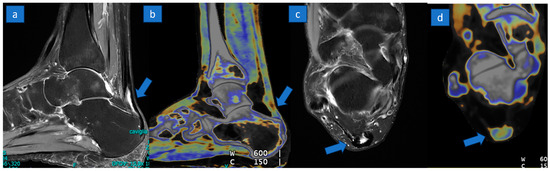

Identification of Achille’s Tendon Tears: Diagnostic Accuracy of Dual-Energy CT with Respect to MRI

3.3. DECT Results